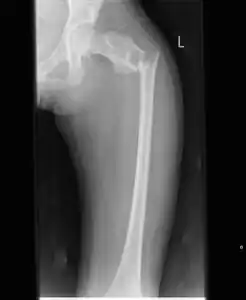

Simple bone cysts are often found incidentally on X-rays. About 90 to 95% of the lesion is found in metaphysics of long bones. The cyst is centered, oblong in shape along the long axis of a long bone. Rarely, they are large and multicameral and are found in diaphysis. When fracture is present, there may be a small bone fragment migrated in the cystic fluid. This is called "fallen fragment sign" which is diagnostic of simple bone cyst. Besides, a bubble migrating upwards (known as "rising bubble sign") is another feature suggesting of simple bone cyst.[7]

- Break through simple bone cyst in the long bone of the thigh, near the hip.